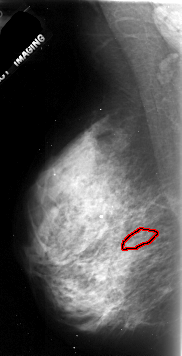

FILE: A_1072_1.LEFT_MLO.OVERLAY

TOTAL_ABNORMALITIES 1

ABNORMALITY 1

LESION_TYPE CALCIFICATION TYPE PLEOMORPHIC DISTRIBUTION LINEAR

ASSESSMENT 4

SUBTLETY 2

PATHOLOGY MALIGNANT

TOTAL_OUTLINES 1

BOUNDARY